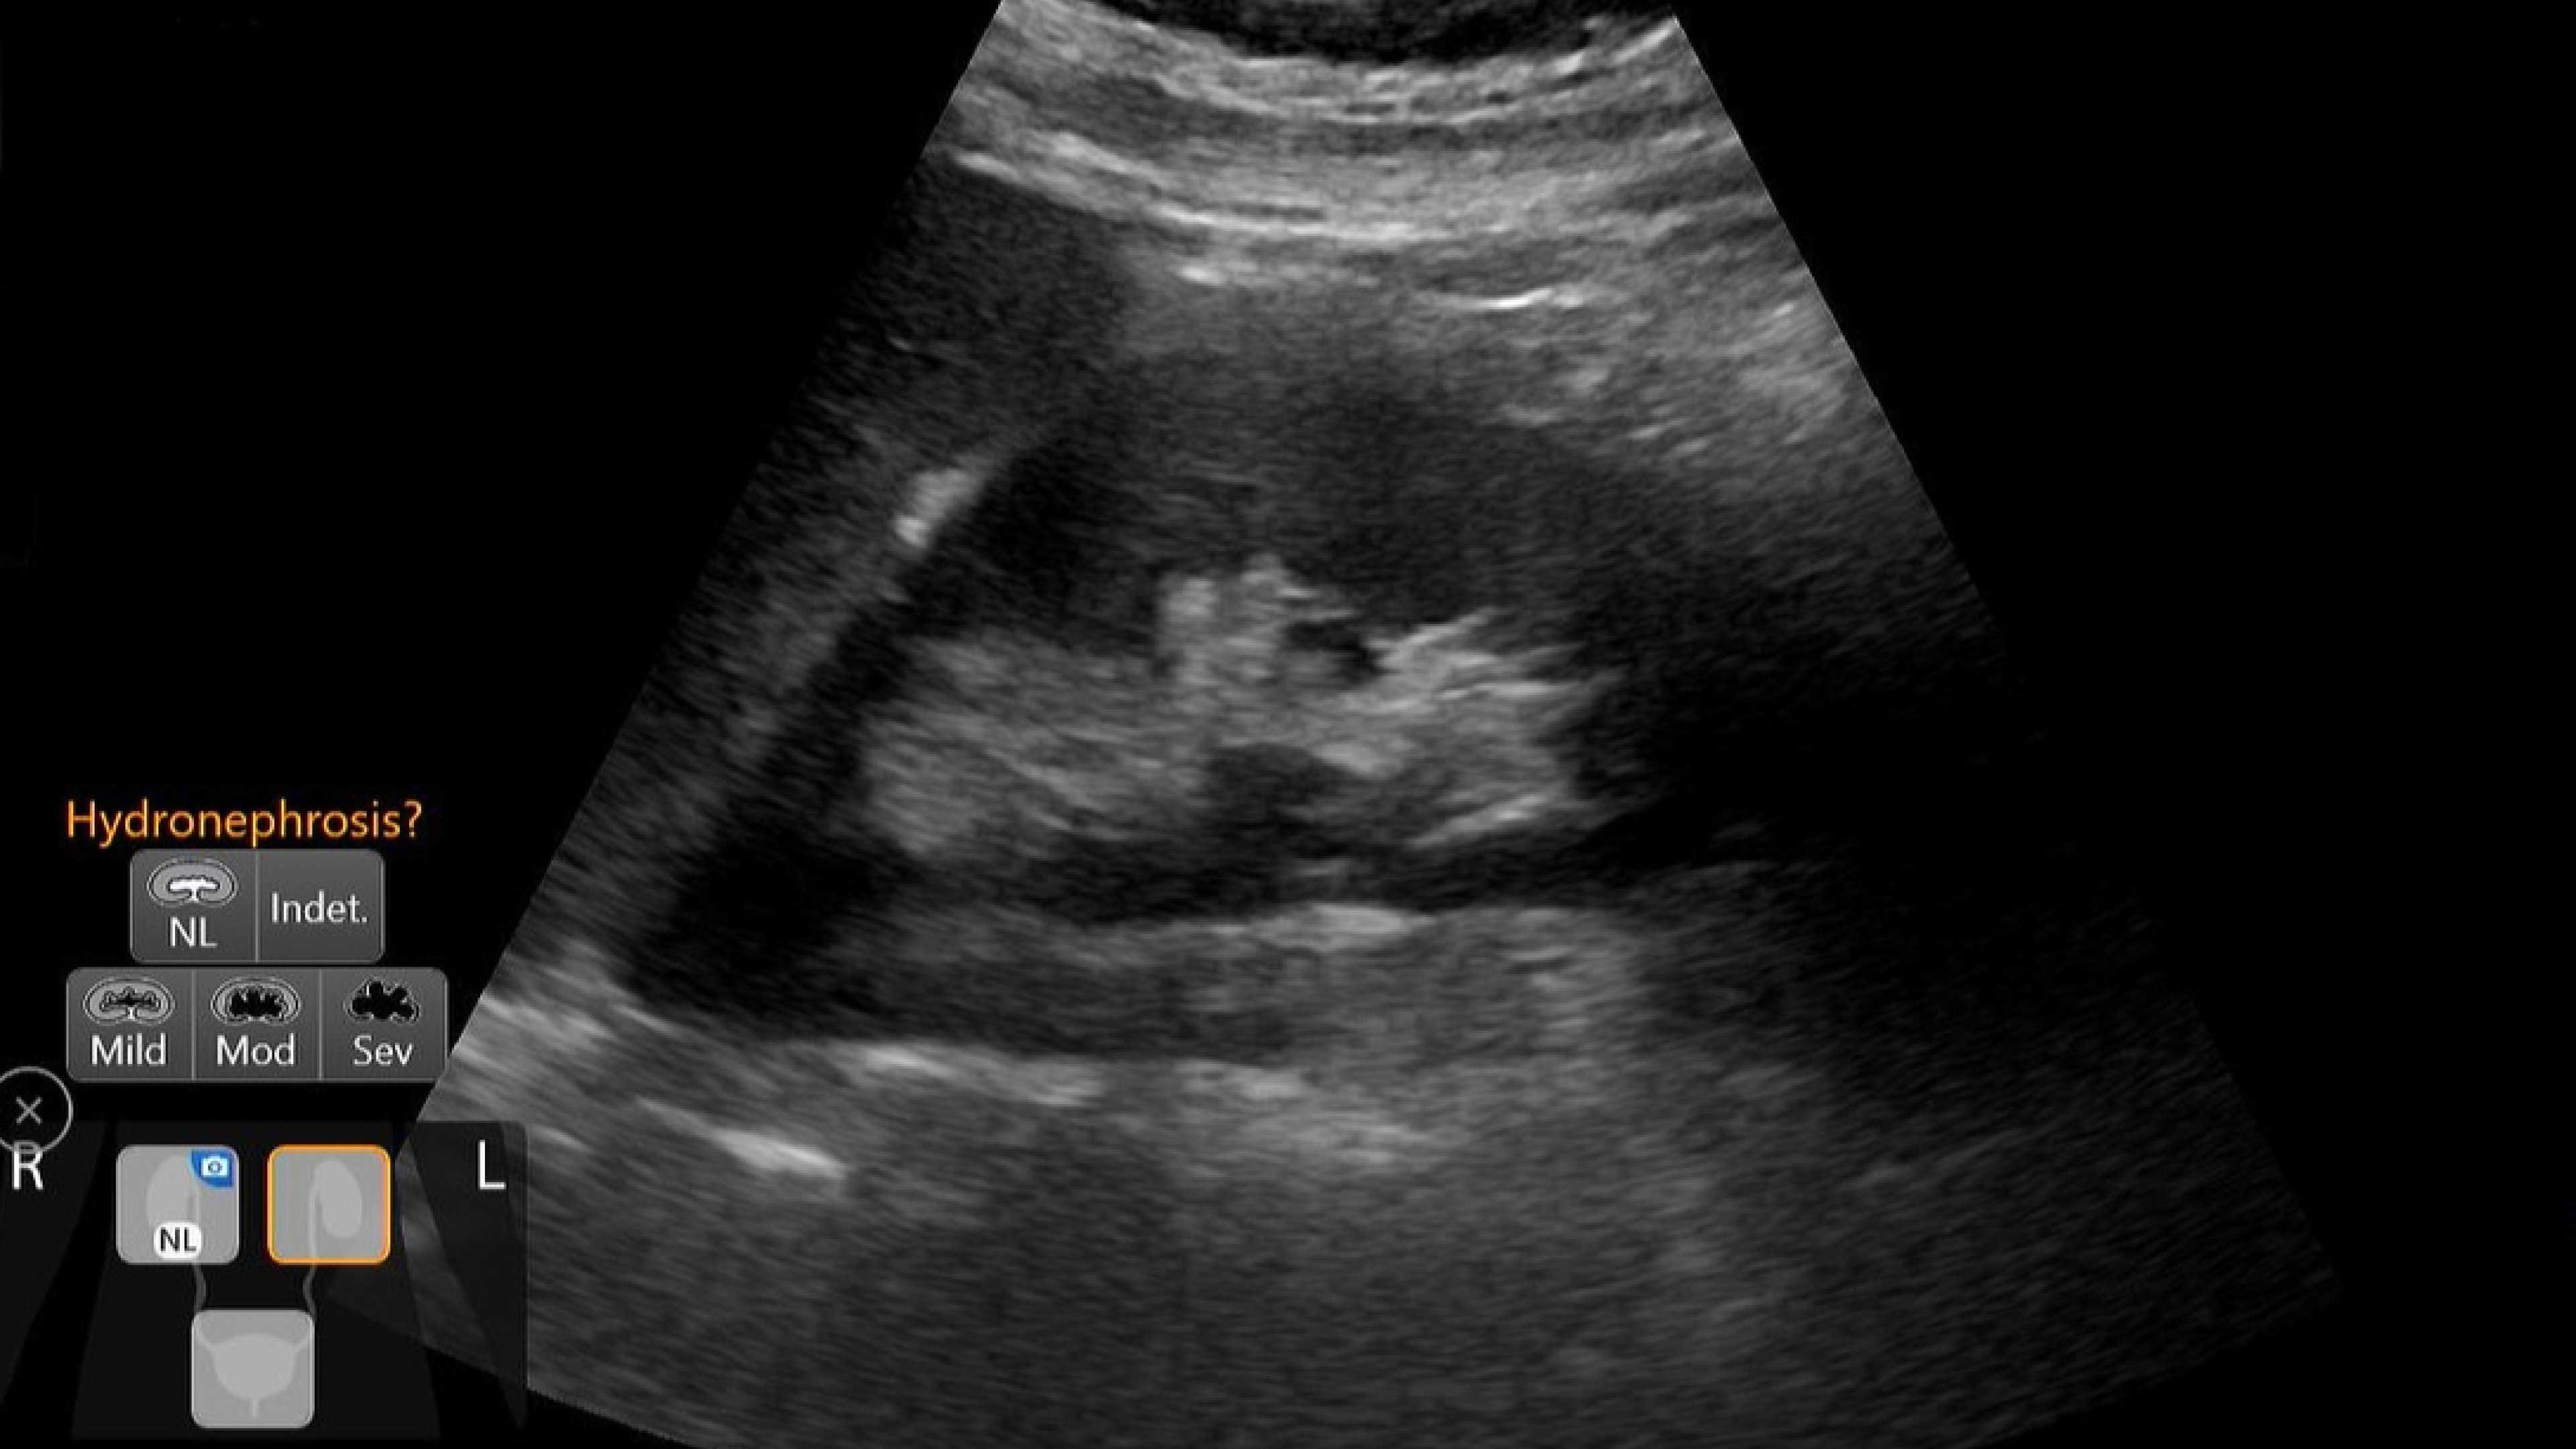

Small yet powerful

Flexible, wireless dual-probes deliver clear images and Venue family software